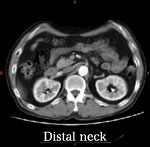

Pre-operative CAT scan

AAA size 5.2 cm

AAA stent graft(Cook Zenith) + Lt iliac stenting + Lt internal iliac embolization

平成11年、腹部大動脈瘤を指摘された。

平成18年1月CTにて増大傾向を認め当院紹介受診。

74歳 HCC→TAE

高血圧(+) 糖尿病(−) 喫煙歴(−)

【治療計画】